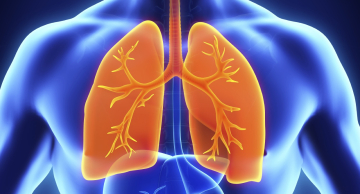

Programa Inspire do HC de Botucatu retoma atividades em 2025